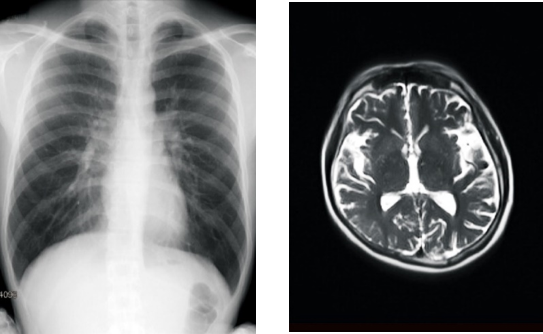

【「カルテコ」で閲覧できるようになる検査画像のイメージ】

賛育会病院では2021年10月11日より、「カルテコ」で健診情報が閲覧可能になりました。今回新たに、健診・人間ドックで撮影したレントゲン・マンモグラフィ・CT(コンピュータ断層撮影)・MRI(磁気共鳴画像診断)などの検査画像が閲覧できるようになります。21年1月以降の過去のデータまでさかのぼって閲覧することができます。